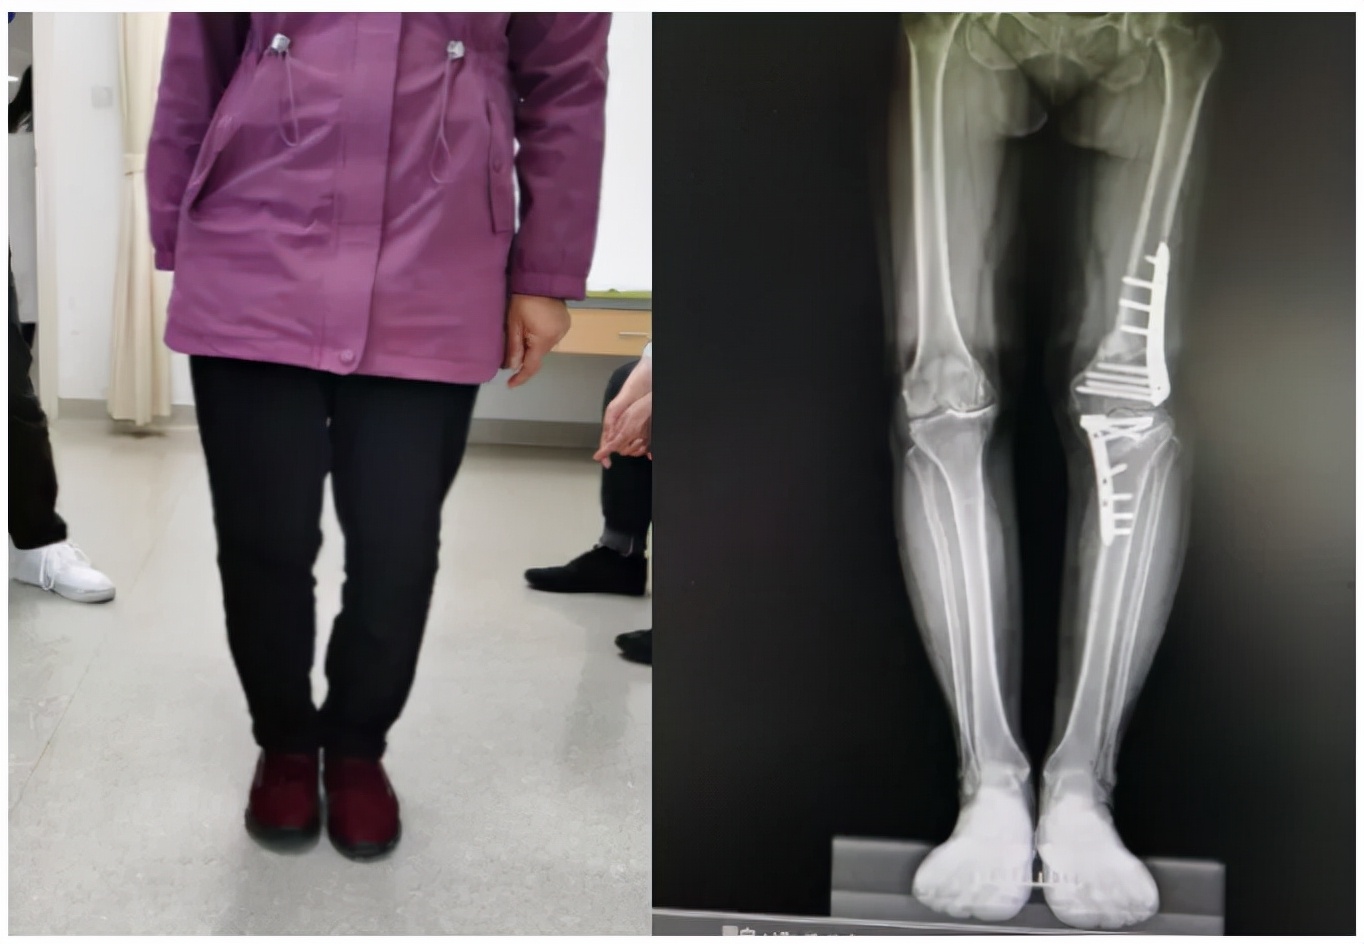

术后半年

术后1年